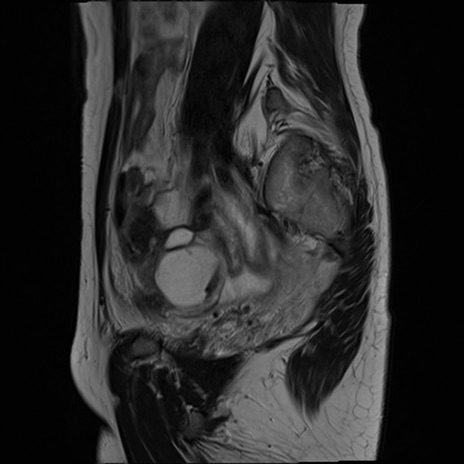

症例39 T2WI(矢状断像)

MRI(4日後)